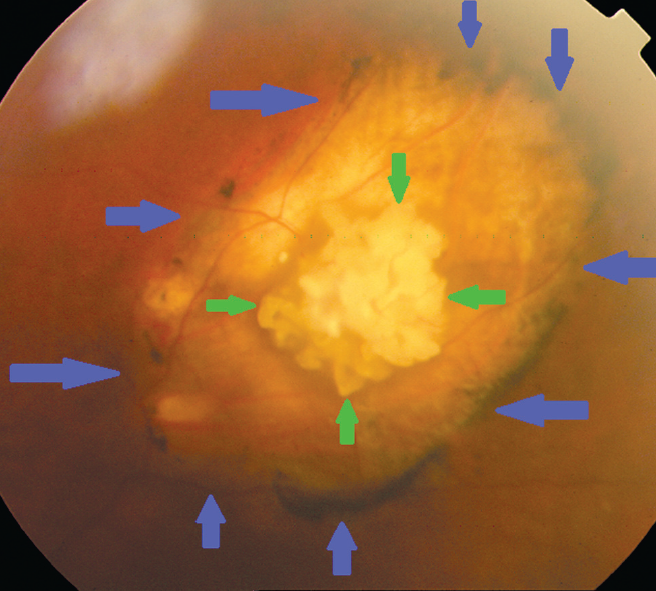

Three years after the initial visit, one patient presented a second focus that was revealed on the fundus (Fig. 2). It should be noted that additional calcifications in the Achilles tendon of this patient were simultaneously revealed.

Fig. 2. Fundus photo of patient Sh., 59 years old at first visit, and after 38 months follow-up (green arrows – borders of the first focus, blue arrows – borders of the second focus)

Рис. 2. Фото глазного дна пациентки Ш., 59 лет: при первом осмотре (а) и через 38 мес. (b) (границы первого очага — зелёные стрелки, границы второго очага — синие стрелки)

Three female patients aged 59, 72, and 73 years, respectively, had indications of a systematic process in history, namely changes in the biochemical analysis of their blood indicating a mineral metabolism disorder, deposition of calcifications in their soft tissues (muscles, tendons), whereas the patient of 72 years old was also diagnosed with bilateral multifocal eye lesion. Furthermore, and in the latter patient, the patient suffered from multiple spontaneous fractures. On the other hand, the remaining two cases (male patients aged 64 and 69 years old) exhibited no abnormalities in their biochemical analysis of blood.